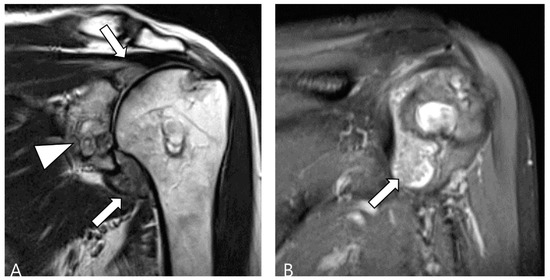

2.3. Morphological Findings for D-TSGCT

2.4. Relationship to Adjacent Structures of D-TSGCT